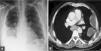

Caso 3Mujer de 50 años, exfumadora, con antecedentes de carcinoma de colon en estadio IV, intervenido quirúrgicamente 7 años atrás, con varias líneas de quimioterapia y en progresión. Ingresó por un cuadro de 3 días de evolución consistente en fiebre de 39°C, tos, expectoración purulenta y dolor de tipo pleurítico en el hemitórax derecho, con semiología de derrame en los 2 tercios inferiores de hemitórax. La radiografía de tórax y la TC mostraban derrame pleural bilateral, de predominio derecho, con loculaciones en su porción superior, infiltrado pulmonar en el lóbulo inferior derecho con áreas de abscesificación y múltiples nódulos pulmonares en relación con metástasis ya conocidas (fig. 2). La toracocentesis mostró un líquido serohemático, espeso, con crecimiento de G. haemolysans sensible a penicilina, cefalosporinas y aminoglucósidos. La paciente fue tratada con tubo torácico (1.670ml) y fibrinolíticos junto con amoxicilina-ácido clavulánico (1g i.v. cada 8h) y levofloxacino (500mg cada 12h, i.v.) durante 10 días, tras los cuales se pasó a la administración oral (amoxicilinaácido clavulánico: 875/125mg cada 8h; levofloxacino: 500mg cada 24h), hasta completar un total de 21 días. La evolución tanto clínica como radiológica fue favorable.

Tomografía computarizada de tórax del caso 3, en la que se objetiva derrame pleural bilateral, de predominio derecho, con loculaciones en su porción superior, infiltrado pulmonar en el lóbulo inferior derecho con áreas de abscesificación y múltiples nódulos pulmonares en relación con metástasis ya conocidas.